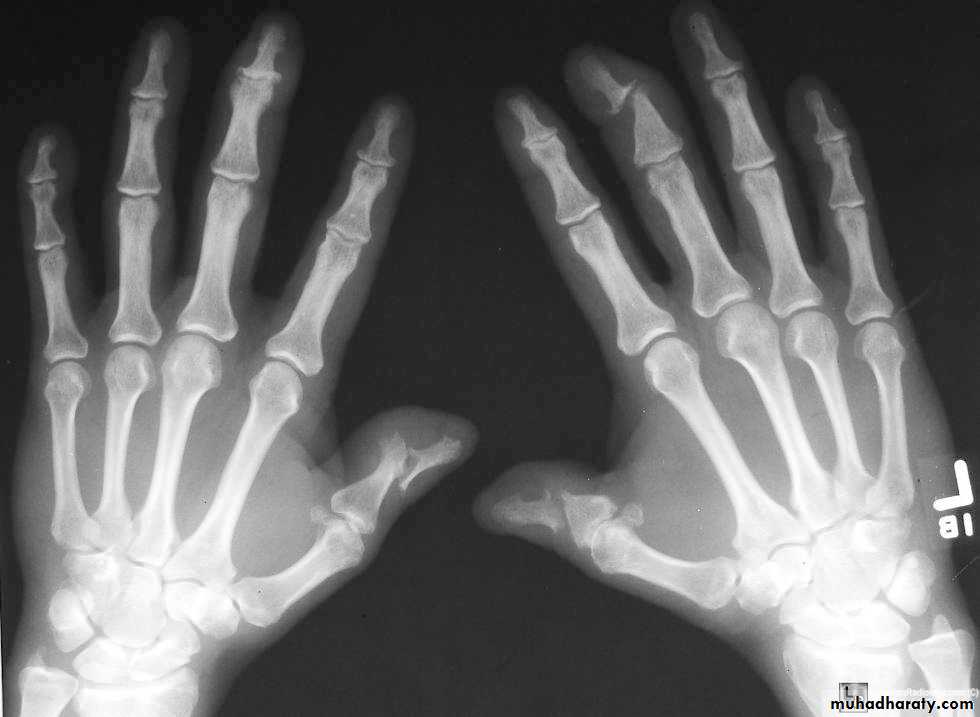

Shows many features similar to RA but erosions are less prominent . the knee , ankle and wrist are the joints most commonly affected .psoriasis

There is an erosive arthreopathy with predominant involvement of the terminal interphalangeal joints.Gout :

In gout ,the deposition of the urate crystals in the joint & in the adjacent bone gives arise to an arthritis which most commonly affects the metatarsophalangeal joint of the big toe .Radiological changes involving :

1.soft tissue swelling 2 . erosions 3 . usually no osteoporosis .4 . Tophi.